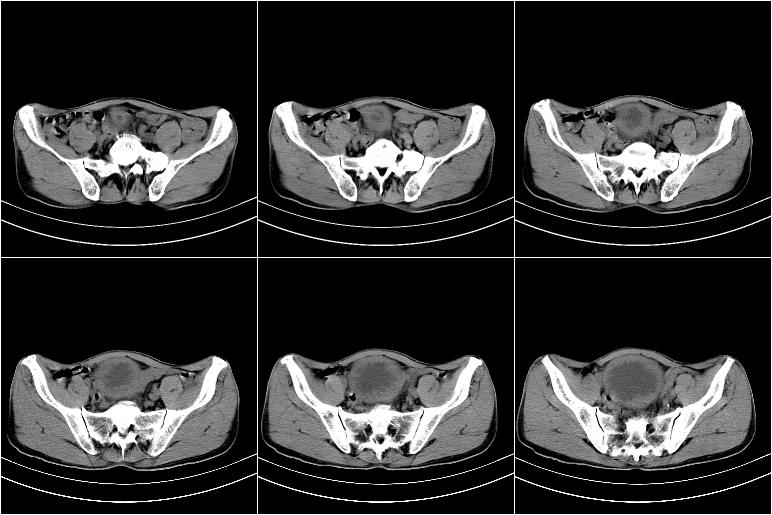

标题: CT21568:男,57岁,双肾及输尿管重度积水。彩超示前列腺占 [打印本页]

标题: CT21568:男,57岁,双肾及输尿管重度积水。彩超示前列腺占

考虑前列腺增生并慢性尿潴留致膀胱肌小梁增生

考虑膀胱癌侵犯双侧输尿管末端及前列腺,双输尿管扩张积水。

前列腺增生肥大,内密度不均,ca不排外;膀胱壁弥漫性增厚,膀胱精囊三角清,炎症?

前列腺ca;膀胱炎,膀胱、直肠受累不除外

考虑膀胱癌侵犯双侧输尿管末端及前列腺,双输尿管扩张积水.

1 前列腺增生肥大,不除外癌变可能,建议mr检查

2 膀胱壁弥漫性增厚,内侧可见增粗的小梁和腺体,考虑为腺性膀胱炎

前列腺增生,内密度不均,警惕癌变,膀胱壁弥漫性增厚,考虑慢性膀胱炎。

考虑前列腺增生症并腺性膀胱炎,双侧输尿管扩张;建议必要时行mri检查。